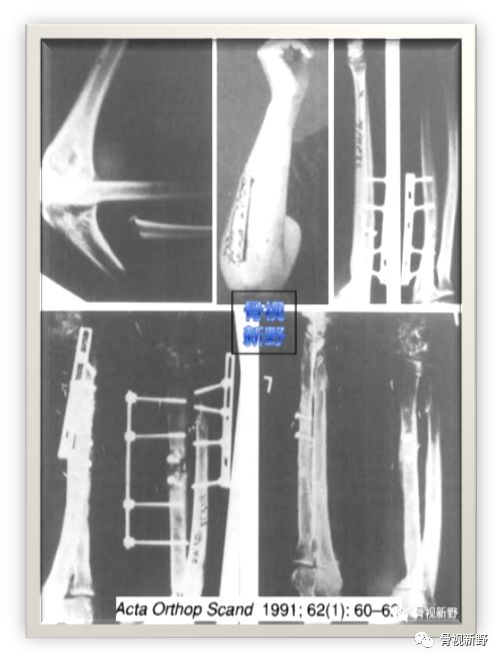

1984年,荷兰医生Rene K.Marti 等人首次报道了将AO钢板(DCP/圆孔钢板)用于开放性骨折及感染性骨不连的外固定,取得了较好的疗效。

Cases

后来,Ramotowski 和 Granowski (1987) 对该技术进行了发展,称为ZESPOL接骨术。

1991年,Rene K.Marti等人再次报道了将AO钢板作为外固定架用于开放性骨折以及骨感染性的固定病例12例,也取得了较好的疗效。